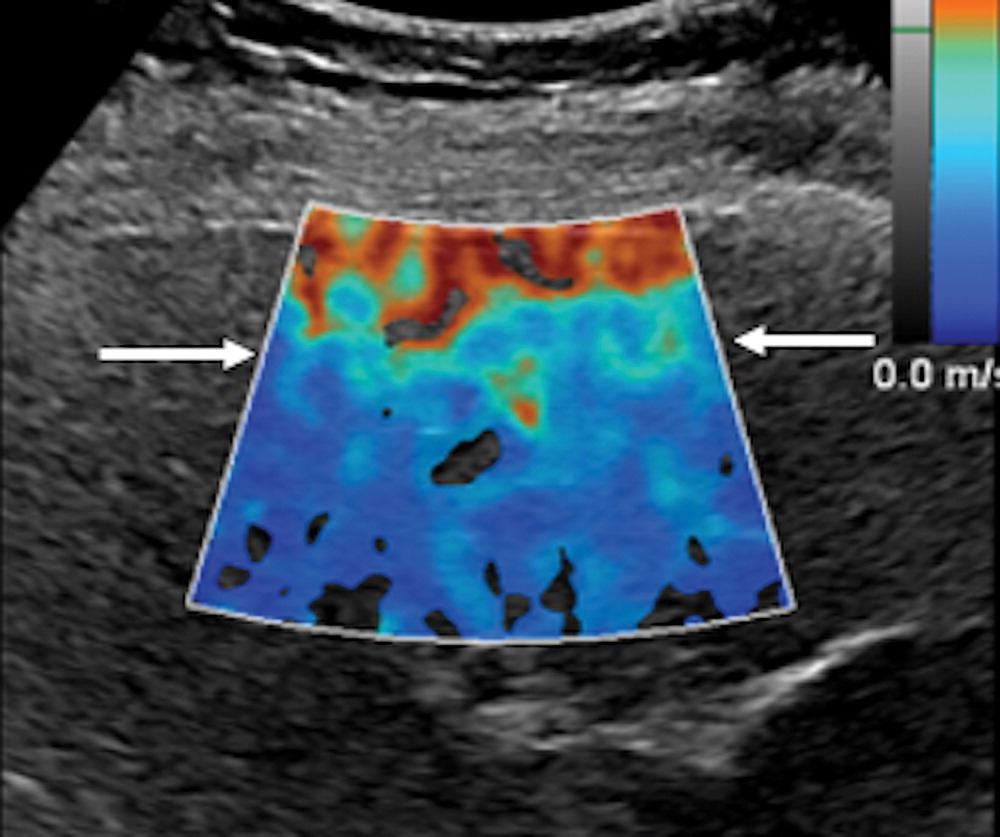

La elastografía por ondas de corte (SWE) ha demostrado ser una técnica esencial para la evaluación no invasiva de la rigidez del hígado. Tecnologías como la elastografía transitoria controlada por vibración (VCTE) y el impulso de radiación acústica (ARFI) han mejorado la precisión de las mediciones, permitiendo una evaluación más detallada de las condiciones hepáticas.

Para obtener mediciones confiables, se recomiendan al menos diez tomas en elastografía puntual (pSWE), aunque estudios indican que cinco mediciones pueden ser suficientes si cumplen con los criterios de calidad (relación intercuartil/mediana menor al 30%). En elastografía bidimensional (2D SWE), la mayor área de medición permite que cinco mediciones sean adecuadas, siempre que se utilicen las herramientas de evaluación de calidad proporcionadas por el fabricante.